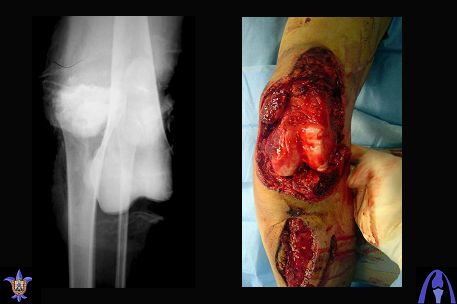

[Ortho] open dislocation of the knee joint

Снимки прошлых публикации из моего Power point

Djoldas Kuldjanov, MD

Department of Orthopedic Surgery

St. Louis University Medical Center

Имя     : knee dislocation 1.jpg

Имя     : knee dislocation 2.jpg

Имя     : knee dislocation 3.jpg